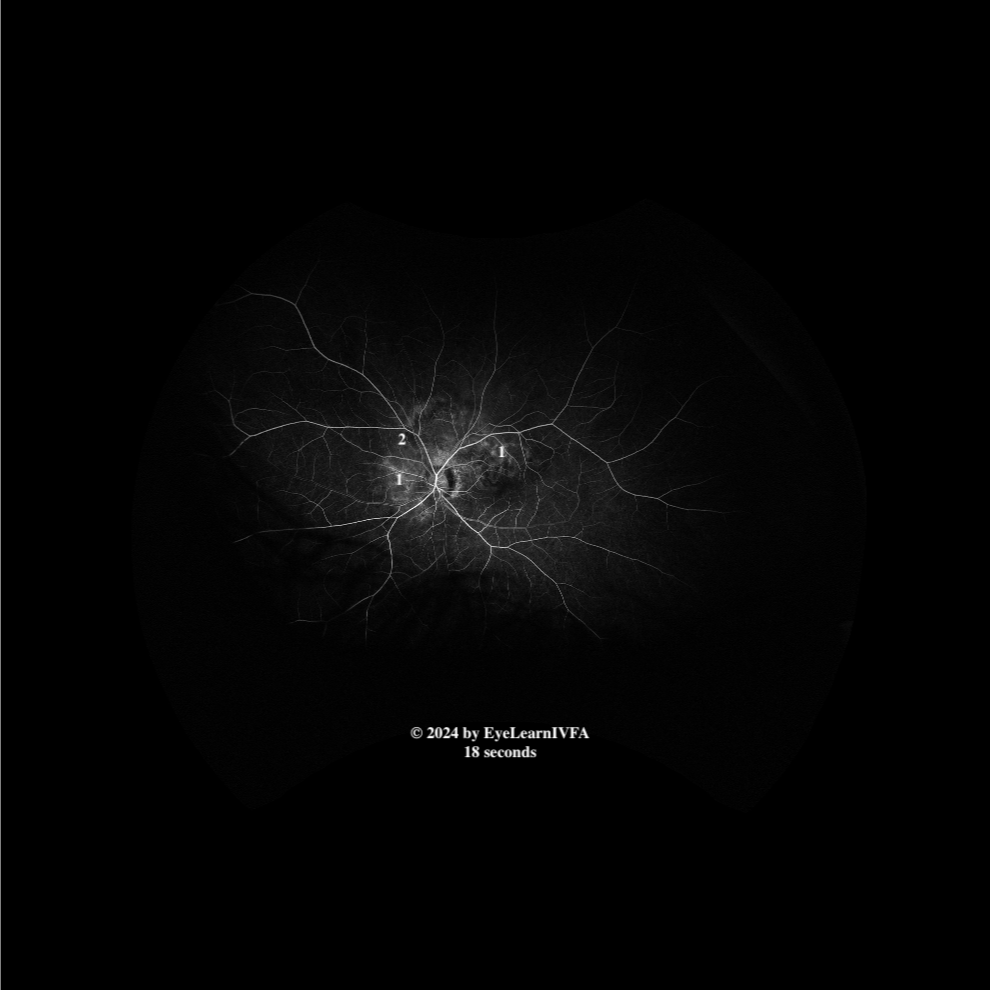

• IVFA OS at 18 seconds

Early to mid arteriovenous phase.

Key features include:

• Subtle areas of hypofluorescence (2),  with increasing surrounding marginal fluorescence, again respecting a peripapillary disruption (1).

• No obvious retinal vessel staining to indicate vasculitis.